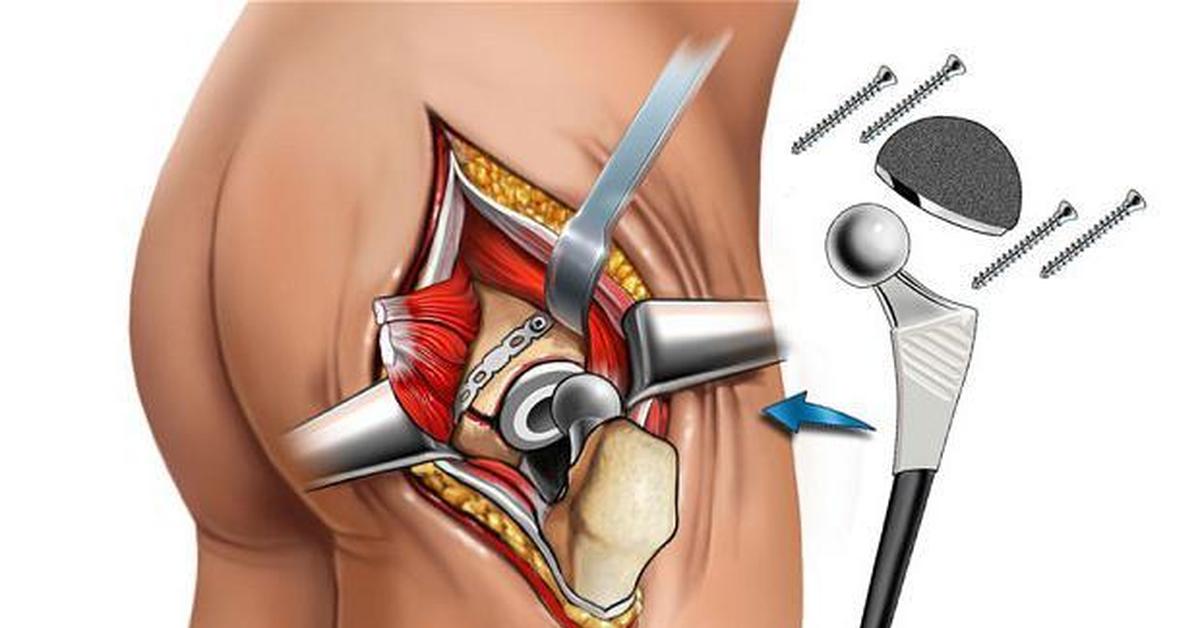

Фотографии и примеры протезирования коленного сустава